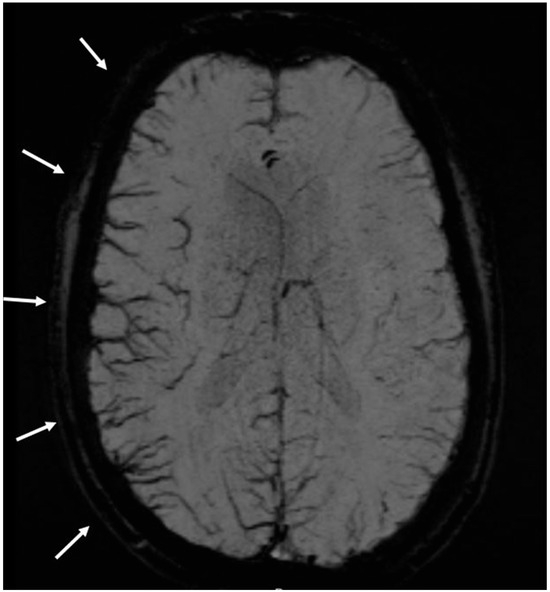

- Kellner-Weldon, F.; Lehmann, V.F.; Breiding, P.S.; Grunder, L.; Muri, R.; Pastore-Wapp, M.; Bigi, S.; Wiest, R.; El-Koussy, M.; Slavova, N. Findings in susceptibility weighted imaging in pediatric patients with migraine with aura. Eur. J. Paediatr. Neurol. 2020, 28, 221–227. [Google Scholar] [CrossRef]

- Scutelnic, A.; Petroulia, V.; Schraml, L.; Jung, S.; Branca, M.; Beyeler, M.; Fischer, U.; Wiest, R.; Slavova, N.; Schankin, C.J. The “Index Vein” as a sign for migraine aura in the emergency setting. Cephalalgia 2023, 43, 3331024221132010. [Google Scholar] [CrossRef]

- Slavova, N.; Denier, N.; El-Koussy, M.; Wiest, R.; Kellner-Weldon, F.; Fischer, U.; Schankin, C.J. The index vein pointing to the origin of the migraine aura symptom: A case series. Neurology 2020, 94, e2577–e2580. [Google Scholar] [CrossRef] [PubMed]